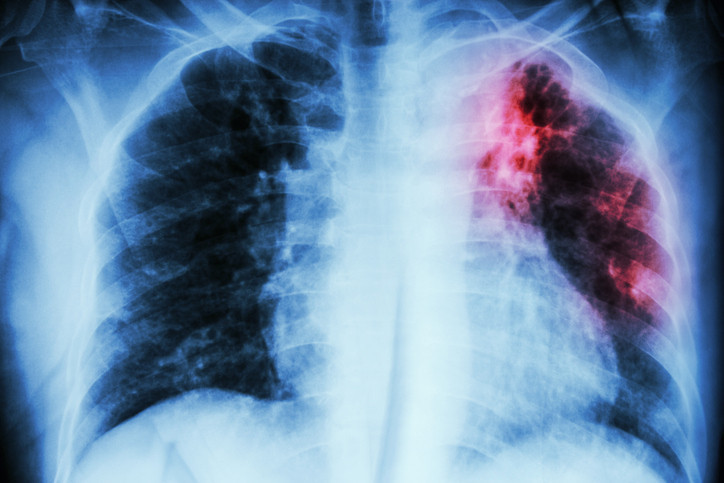

‘Yürüyen zatürre’ ve gençlerdeki risk

Bağışıklık uzmanı Dr. Samira Jeimy, son dönemde özellikle gençlerde ‘yürüyen zatürre’ (mycoplasma pneumoniae) vakalarında devasa bir artış gördüğünü belirtiyor.

Yürüyen zatürre, hafif bir akciğer enfeksiyonudur. Belirtileri arasında boğaz ağrısı, hapşırma, öksürük, baş ağrısı, hafif titreme ve düşük dereceli ateş bulunuyor.